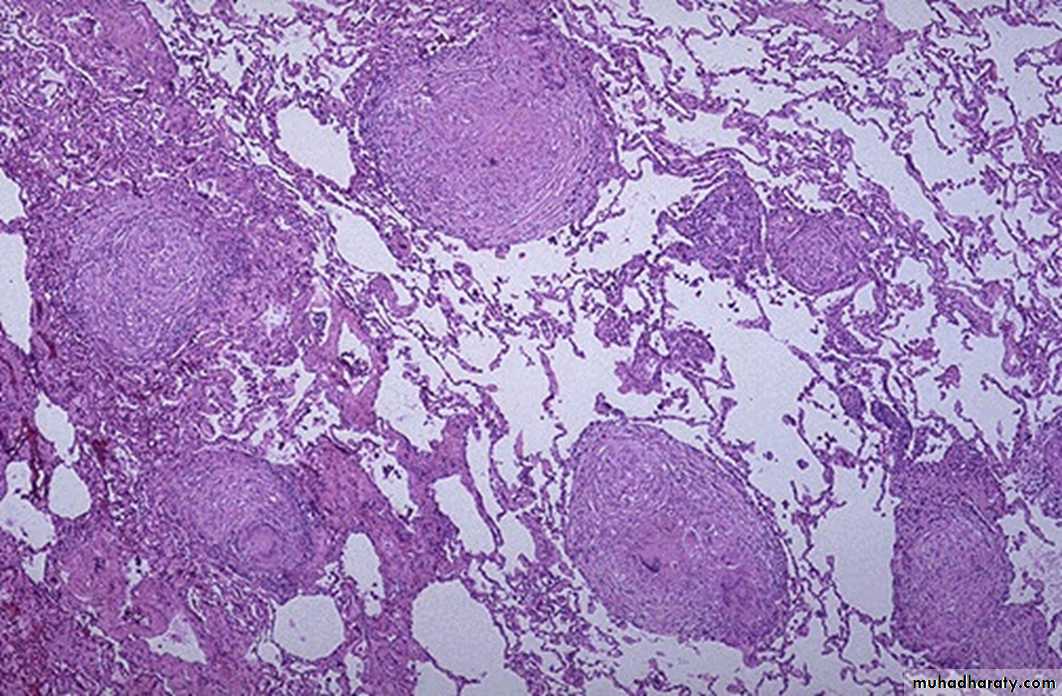

30 years female with fever and shortening of breathing.

1- define the lesion?Granulomatous inflammation

2- What are the main Cells and Mediators of this lesion?